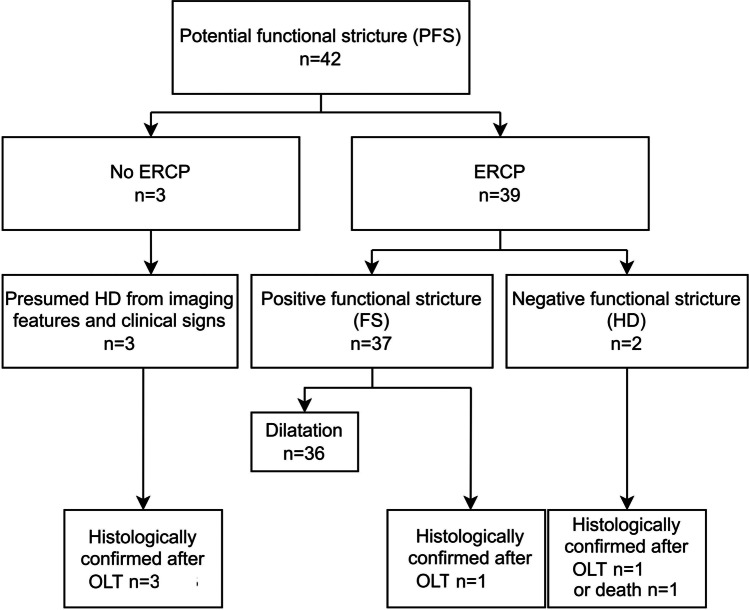

Forty-four (34.1%) ERCPs were performed, 39 in PFS (92.9%) and five in NFS (5.7%) patients due to clinical suspicion. FS was confirmed within 1.7 months (mean) post-MRI in 37 of 39 PFS patients. Thirty-six patients had therapeutic ERCP; the last patient underwent OLT 5 months later. Two PFS patients had no stricture on ERCP and were presumed to have HD. This was confirmed within 6 months; at post-mortem in one, and at OLT in the other. Regarding the three PFS (7.1%) patients who did not have ERCP, all had histologically confirmed HD, but no FS at OLT (Fig. 4).